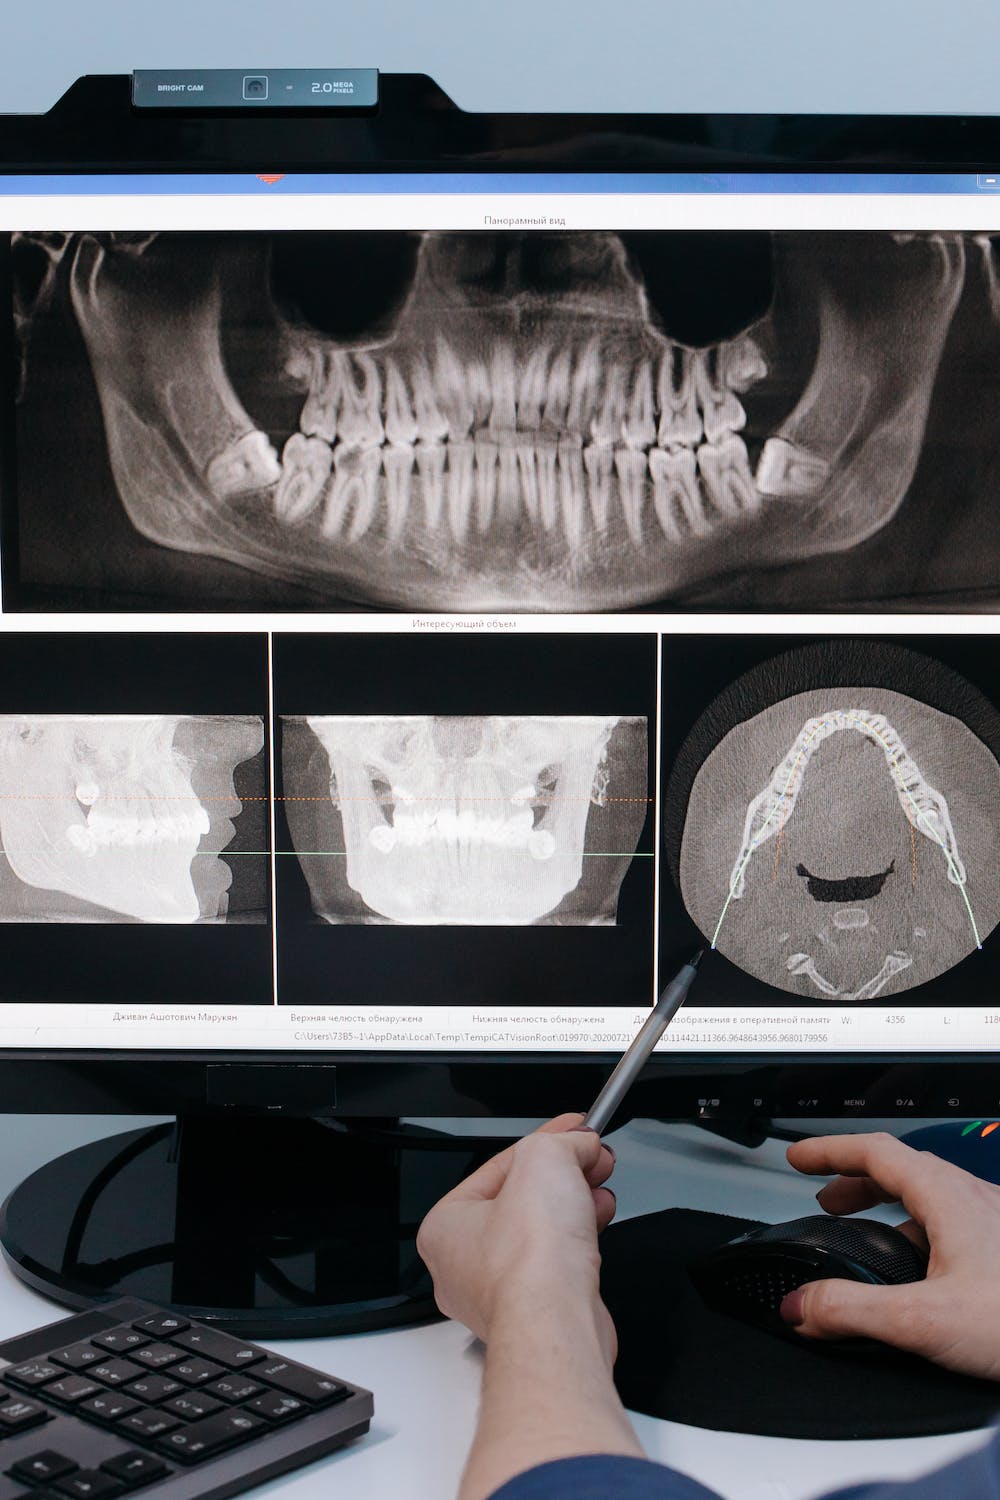

오늘은 턱관절의 기능 이상으로 인해 발생하는 문제로, 턱통증, 귀뚜라미 소리, 턱관절의 제한 등으로 일상생활에서도 상당한 불편을 끼칠 수 있는 턱관절장애에 대하여 알아보겠습니다.

턱관절은 모든 턱운동의 중심축으로 작용하며 턱 근육과 인대에 의해 지지 되는데, 이때 턱관절 사이에 있는 디스크는 뼈와 뼈 사이의 쿠션 역할을 하게 되며 이러한 근육과 인대, 디스크, 턱뼈가 함께 어우러져 개구(입 벌리기)와, 저작(씹는 행위), 말하기, 삼키기 등의 복합적인 활동을 담당하게 되는데, 여러 요인에 의해 이러한 턱관절 기능에 이상이 생긴 것을 턱관절 장애 또는 악관절 장애라고 합니다.

3. 턱관절장애의 증상

턱관절 장애의 대표적인 증상으로 통증을 들 수 있는데, 음식을 씹거나 하품할 때 양쪽 귀 앞의 아래턱뼈와 저작 근육에 통증을 느끼게 되며 또한 입을 열 때마다 턱 관절에서 소리가 나며(관절 잡음), 입과 턱의 움직임이 제한되어 집니다(하악운동 제한).